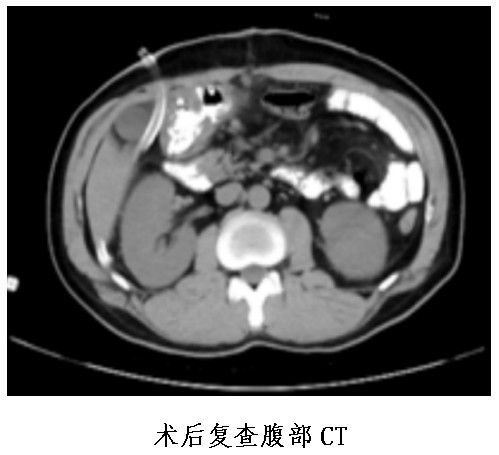

普外中心主任兼胃腸外科主任譚曙光組織醫(yī)師團(tuán)隊(duì)就患者治療方案進(jìn)行討論,認(rèn)為該名胃體神經(jīng)內(nèi)分泌瘤患者,符合手術(shù)指征。經(jīng)過反復(fù)評估并與患者本人及家屬溝通,最終譚曙光醫(yī)師團(tuán)隊(duì)決定摒棄傳統(tǒng)的胃切除術(shù),選擇腹腔鏡根治性近端胃切除+D2淋巴結(jié)清掃及雙通道吻合(食道空腸over-Lap吻合及空腸遠(yuǎn)端胃吻合)術(shù),有效減少了反流性食道炎等術(shù)后并發(fā)癥的發(fā)生。1月9日,患者完成了手術(shù),術(shù)后恢復(fù)順利并于22日出院。

據(jù)悉,腹腔鏡根治性近端胃切除+D2淋巴結(jié)清掃及雙通道吻合(食道空腸over-Lap吻合及空腸遠(yuǎn)端胃吻合)術(shù),屬于腹腔鏡下IV級高難度手術(shù)。該手術(shù)的優(yōu)點(diǎn)為全部操作均在腹腔鏡下完成,對腹腔干擾少,術(shù)后切口疼痛及腸粘連發(fā)生率明顯減少;能完整切除胃部病灶,最大限度地保留患者的正常胃組織及功能;能大大減少胃切除術(shù)后的嚴(yán)重的胃食管反流性疾病等并發(fā)癥的發(fā)生幾率。